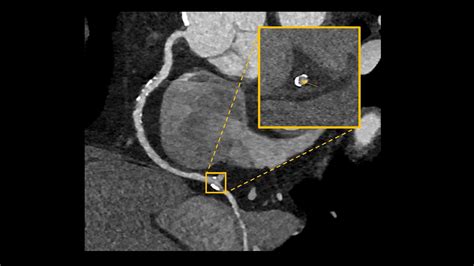

• Assessing heart structures: Looking for congenital heart defects or complications in heart valves.

Once the scan is complete, the images are sent to a radiologist or a specialized cardiologist who analyzes the anatomy of your coronary arteries. They will look for the presence and extent of plaque, the degree of arterial narrowing (stenosis), and the presence of any calcium deposits. You will receive a formal report, and your primary doctor will discuss the findings with you to determine the next steps in your care plan. Depending on the findings, these steps may include lifestyle modifications, cholesterol-lowering medication, or further diagnostic testing.